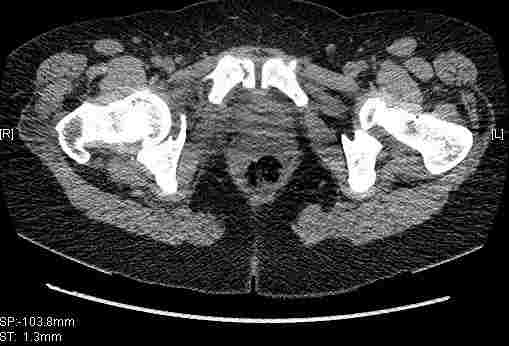

Женщина,58 лет, после ДТП 6 суток. Первично повреждение расценено как переломы ветвей лонной кости. После подтверждения повреждения вертлужной впадины,как чаще всего случается, вопрос встал о тактике. БОльшинство за консерватиное лечение.К сожалению кт у нас "во время" сломался. Прилагаю стандартные снимки вертлужки. У меня следующие вопросы к коллегам:1. Правильно ли рассценивать это повреждение как Т-образный перелом вертлужнй впадины?2. Можно ли добиться анатомической репозиции поверхности вертлужной впадины скелетным вытяжением в данном случае, если нет, что будет этому препятствовать?3. Если смещение останется таким как сейчас, через какое время появится необходимость эндопротезирования (по вашему опыту)?Спасибо.

Удалось сегодня вывести пациентку в соседнюю больницу, где есть кт. Срезы сделаны только горизонтальные.

|